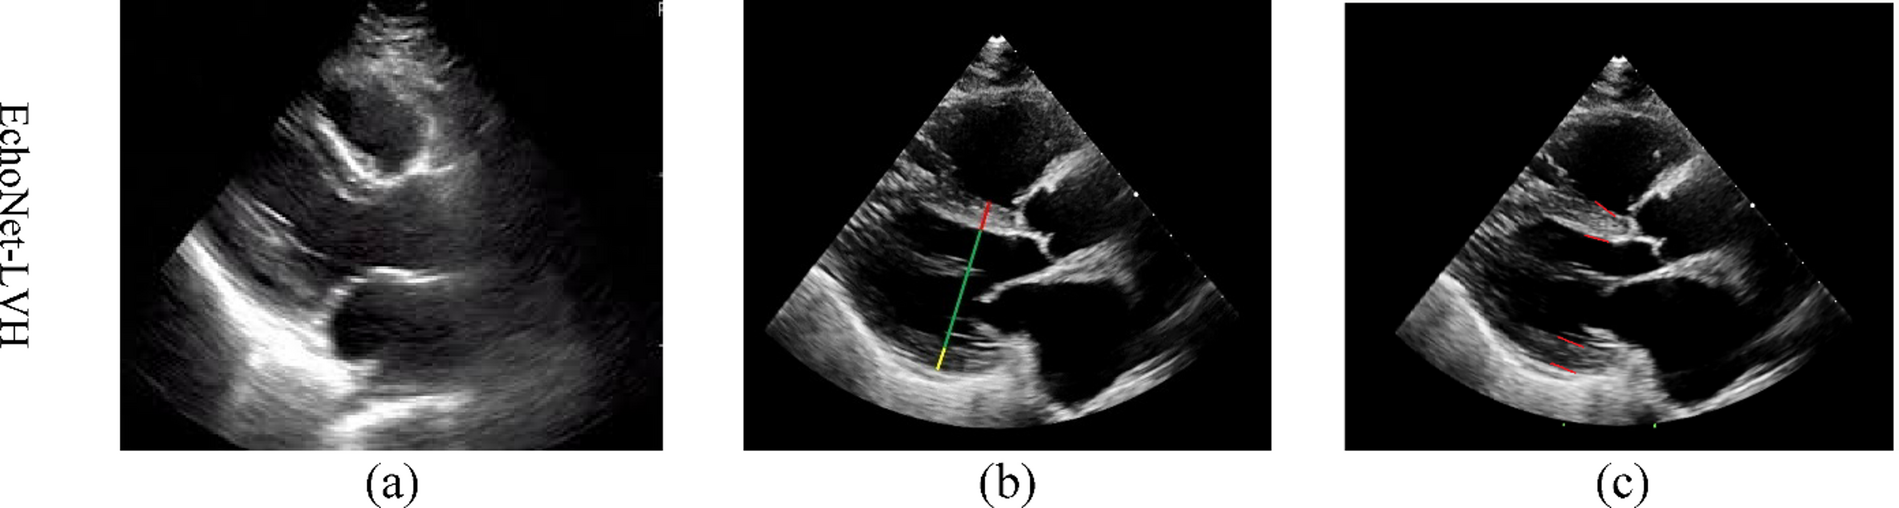

Fig. 9

Visual comparison of the model’s predictions against ground-truth annotations for the keypoint detection task on the EchoNet-LVH dataset. (A) Original input image. (B) Ground-truth keypoints (visualized as lines for IVS, LVID, LVPW). (C) Predicted keypoints generated by our MTL model.